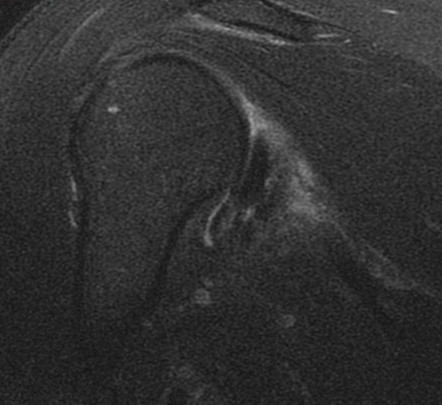

Discussion

Anterior humeral impaction fracture of the lesser tuberosity and posterior labrum tear. The periosteum of the scapula looks intact so maybe should be called a reverse Perthes lesion. Injury occurs when a posterior force occurs to the shoulder (front to back) when the shoulder is internally rotated and flexed. Classic examples are tonic clonic seizure with the patient falling with decorticate rigidity forward and hitting the ground. Also American football lineman in 3 point stance (internal rotation and some flexion) hit by another player moving towards him when the ball is hiked. Typically the other player is as large as a refrigerator.

Diagnosis

Reverse bankart and hill sachs lesions